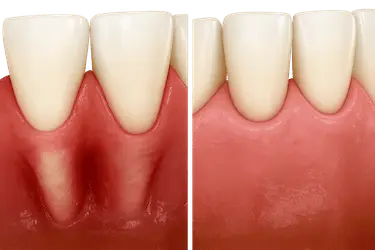

Injerto de encía

El injerto de encía consiste en la extracción de tejido de una zona donante (generalmente, el paladar o una muela del juicio de la arcada superior) para cubrir una zona de raíz visible de un diente o implante.

Ten en cuenta que tus encías pueden retraerse por muchas razones más allá de la enfermedad periodontal. Hablamos, por ejemplo, de una técnica incorrecta de cepillado, del bruxismo o del mantenimiento de hábitos nocivos.